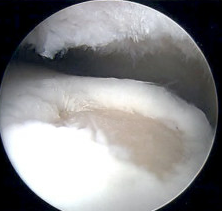

Arthroscopy Approaches

Anterolateral / anteromedial

- anterior 50 - 60% lesions

Anterolateral osteochondral lesion accessible via plantarflexing the ankle